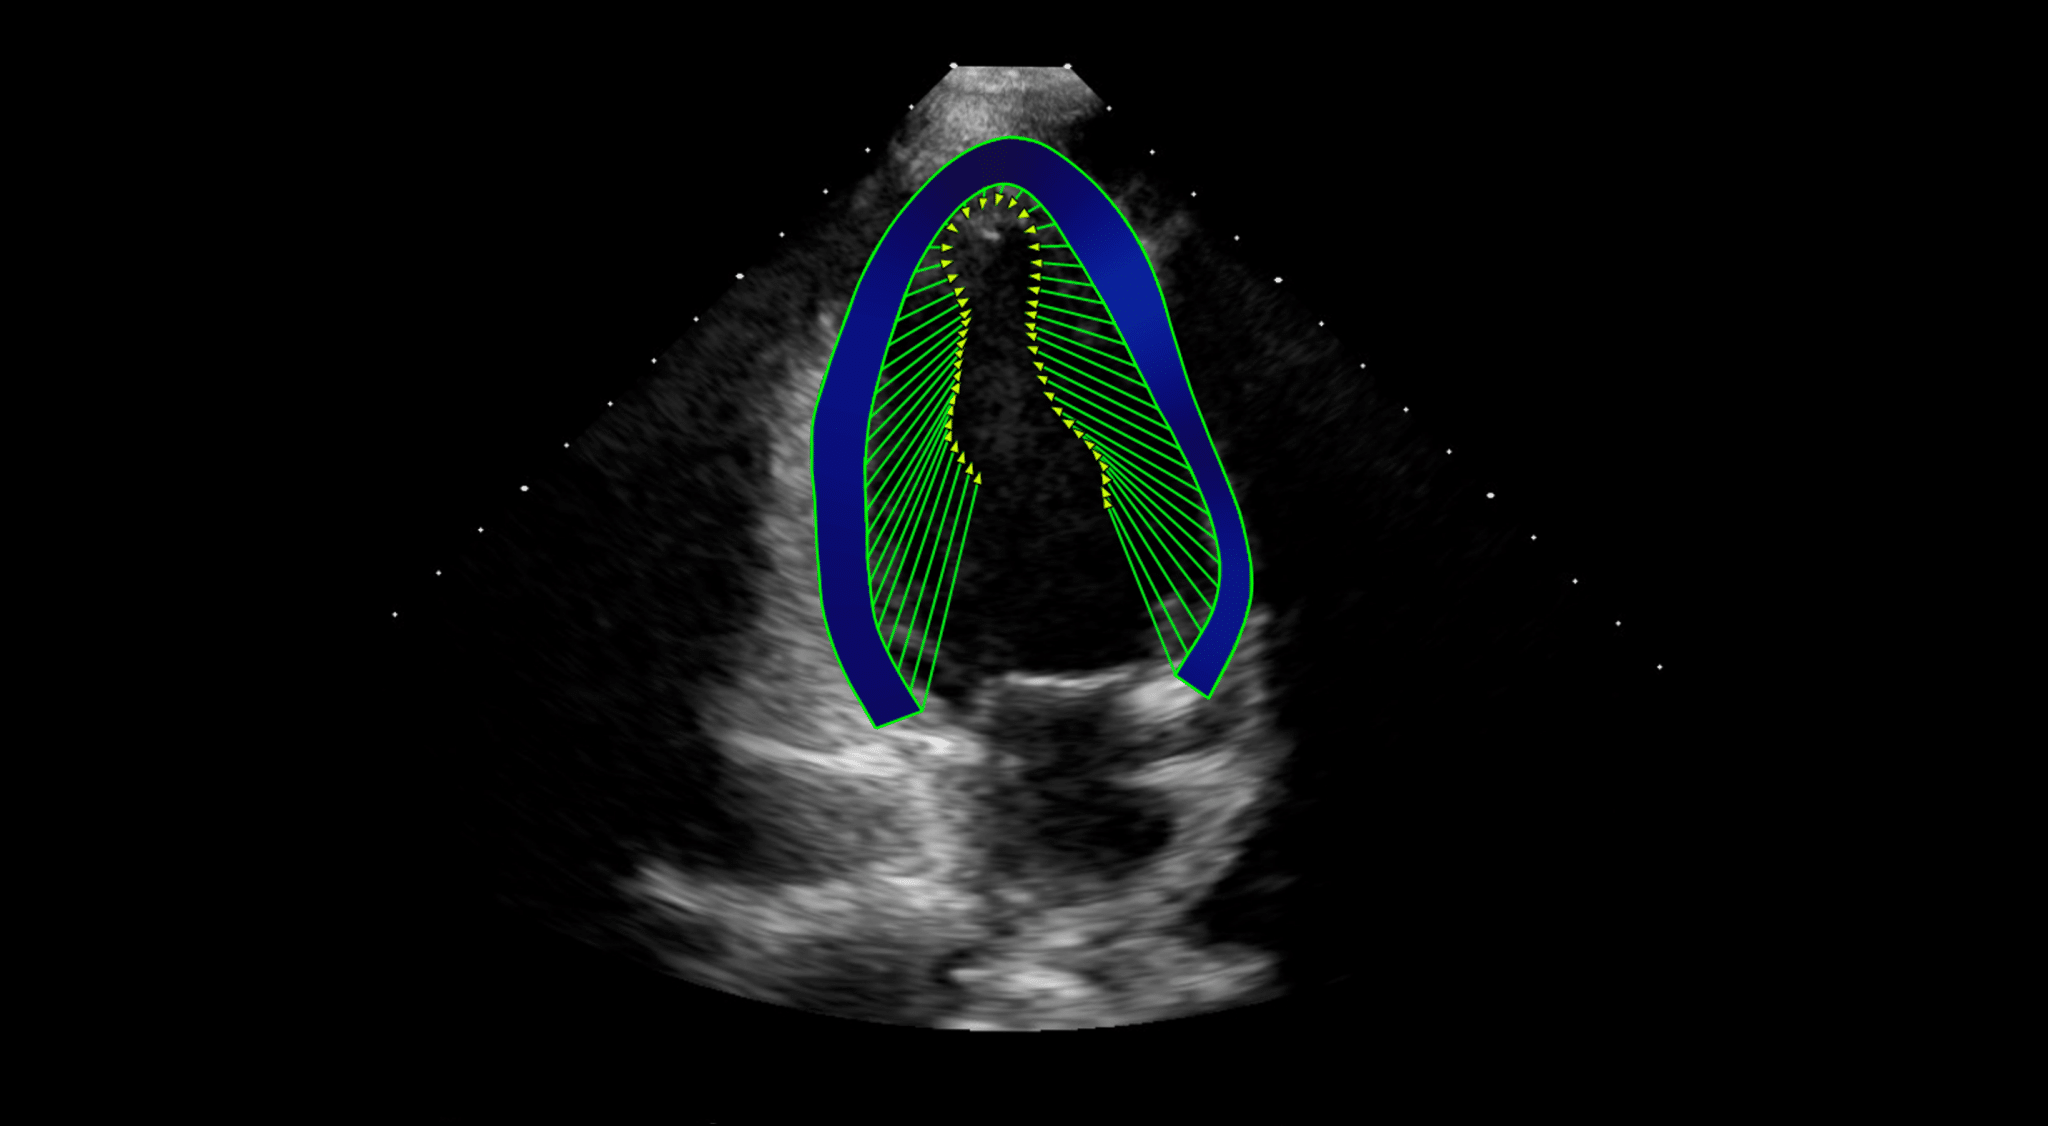

- Allows the quantitative evaluation of the Left Ventricle, Right Ventricle and the Left Atrium OEM solution. See the applications below for further details